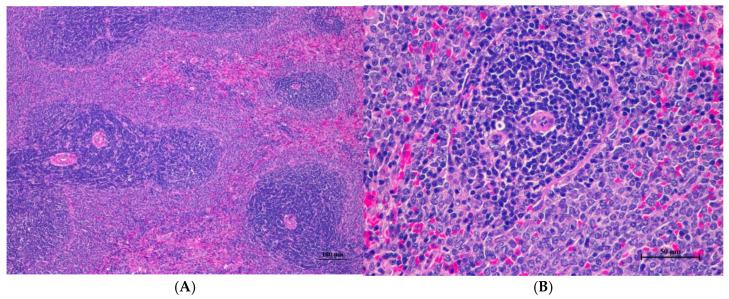

This study rigorously evaluated the safety profile of dietary fiber extracted from cassava pulp, a promising functional food ingredient, through acute and 28-day sub-acute oral toxicity assessments in Wistar rats. This research hypothesized that cassava pulp fiber would exhibit minimal toxicity across a range of doses. In the acute study, rats received single oral doses of 175, 550, or 2000 mg/kg, while the sub-acute toxicity study involved daily doses of 250, 500, or 1000 mg/kg, with satellite groups included for reversibility assessment. Comprehensive monitoring encompassed clinical signs, mortality, body weight, food intake, hematological and biochemical parameters, relative organ weights, and detailed histopathological examination. Remarkably, no treatment-related mortality or overt clinical signs of toxicity were observed in either study. The LD was higher than 2000 mg/kg for the acute study and the no-observed-adverse-effect level (NOAEL) was determined to be 2000 mg/kg for the acute study and 1000 mg/kg for the sub-acute toxicity study, indicating a high margin of safety. While statistically significant alterations were noted in some hematological, biochemical, and relative organ weight parameters, these changes were not considered toxicologically relevant. Notably, histopathological changes in the lungs were observed across all groups, including controls, warranting further investigation. These findings suggest that cassava pulp fiber is well tolerated at high oral doses, supporting its potential for safe application in food and nutraceutical formulations. However, the observed lung alterations necessitate further research to elucidate their etiology and clinical significance.

本研究通过对Wistar大鼠进行急性和28天亚急性经口毒性评估,严格评估了木薯渣中提取的膳食纤维(一种有前景的功能性食品成分)的安全性。本研究假设木薯渣纤维在一系列剂量下毒性极小。在急性研究中,大鼠单次经口给予175、550或2000 mg/kg的剂量,而亚急性毒性研究涉及每日给予250、500或1000 mg/kg的剂量,并设有卫星组进行可逆性评估。全面监测包括临床症状、死亡率、体重、食物摄入量、血液学和生化参数、相对器官重量以及详细的组织病理学检查。值得注意的是,两项研究均未观察到与治疗相关的死亡或明显的毒性临床症状。急性研究的半数致死量高于2000 mg/kg,急性研究的未观察到有害作用水平(NOAEL)确定为2000 mg/kg,亚急性毒性研究的NOAEL为1000 mg/kg,表明安全性很高。虽然在一些血液学、生化和相对器官重量参数中发现了具有统计学意义的变化,但这些变化在毒理学上不被认为具有相关性。值得注意的是,在所有组(包括对照组)中均观察到肺部的组织病理学变化,需要进一步研究。这些结果表明木薯渣纤维在高经口剂量下耐受性良好,支持其在食品和营养保健品配方中安全应用的潜力。然而,观察到的肺部变化需要进一步研究以阐明其病因和临床意义。